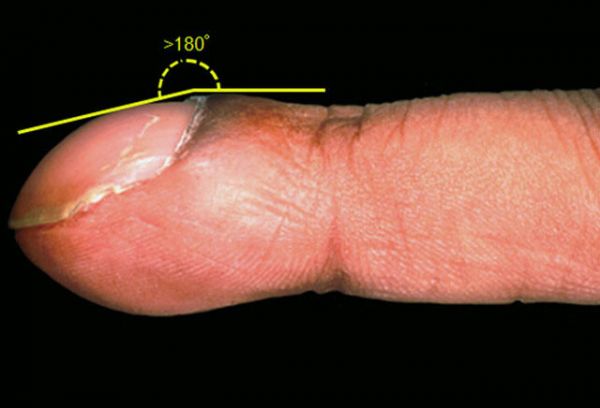

这张图片展示的杵状指,与下列哪种疾病相关?

杵状指与多种潜在的呼吸和心血管系统疾病,以及肿瘤、感染、肝胆系统、纵隔、内分泌及胃肠疾病相关。当近端甲襞与指甲板间的角度(罗维朋角)大于 180°即出现杵状指(如图所示)。

Hamman-Rich 综合征,又称急性间质性肺炎,是特发性间质性肺炎的一种,以肺间质组织炎症为主要特征。当发展到晚期间质性肺病时,就可能出现杵状指(如图)及右心衰。